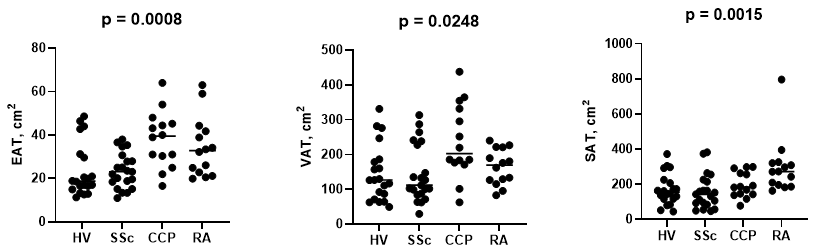

SAT (cm2) was significantly increased in RA (RA: 272 [194-322], HV: 154 [116-221], p=0.0015). VAT (cm2) was significantly increased in anti-CCP+ve patients (CCP: 203 [176-338], HV: 127 [75-185], p=0.0248). EAT (cm2) was significantly increased in SSc (23 [17-29]), anti-CCP (40 [29-46]), and chronic RA (33 [22-42]) versus HV (19 [15-31], p=0.0008).

EAT correlated negatively with PCr/ATP (r -0.33, p = 0.0178) and global longitudinal strain (r -0.38, p=0.0413). Both EAT and VAT correlated positively with male sex, age, BMI, body surface area (BSA), and HBA1c (all p< 0.05). VAT correlated with worse lipid profile (p< 0.05). SAT correlated positively with male sex, BMI, and BSA (all p< 0.05) without impact on cardiac functions.

Conclusion: We report for the first time that epicardial adiposity tissue is associated with subclinical reduction in myocardial energetics and global longitudinal strain in patients with IMIDs and CCP positive patients at-risk of RA. This underlines the importance of CVD risk factor modulation in this patient group, especially when EAT is increased.